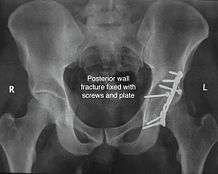

Posterior wall fracture

This is the most common variety of fracture

Cause: Occurs due to dash board injury. When a person travelling in a vehicle involved in head-on collision, the force applied over the flexed knee travels along the femur bone to the head of femur breaking the posterior wall of the acetabulum. The head of the femur is dislocated outside the joint.

If the fragments do not fall into place, or if there are bone pieces in the joint, or if the joint is unstable, surgical fixation using screw(s) and plate(s) is performed